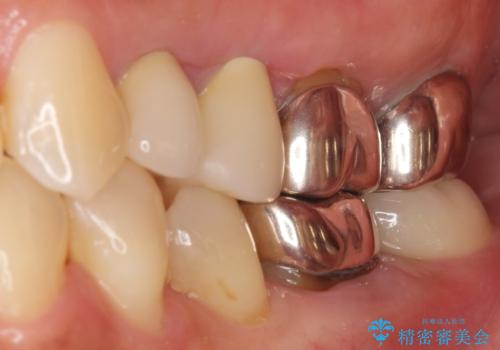

親知らずの移植により、自分の歯を用いて咬合機能を回復することができ、大変喜んで頂けました。

被せ物の種類:オールセラミッククラウン スタンダード

移植後、生着を待って根管治療及び補綴修復を行いました。